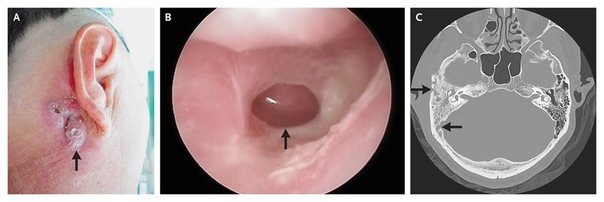

Женщина, 44 года

Жалобы на заложенность в ушах. Ранее у пациентки была выявлена ретркация барабанной перепонки, рекомендовано выполнять пользу Вальсальвы, что временно уменьшало ощущение заложенности.

В течение 6 лет пациентка выполняла упражнение 4 раза в день ежедневно.

При осмотре: в толще барабанных перепонок пузырьки воздуха, признаков отека или воспаления нет. Аудиография: умеренная кондуктивная тугоухость справа, нормальный слух слева.

Вероятнее всего изменения барабанных перепонок вызваны за счет частого выполнения пробы Вальсальвы.

Рекомендовано снизить интенсивность и частоту выполнения пробы.

При осмотре спустя 1 месяц отмечено улучшение.